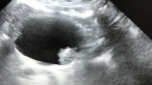

Formation d'échographie pour le médecin généraliste ( initiation ou en perfectionnement )

cours théoriques + pratique de l'échographie en petit groupe